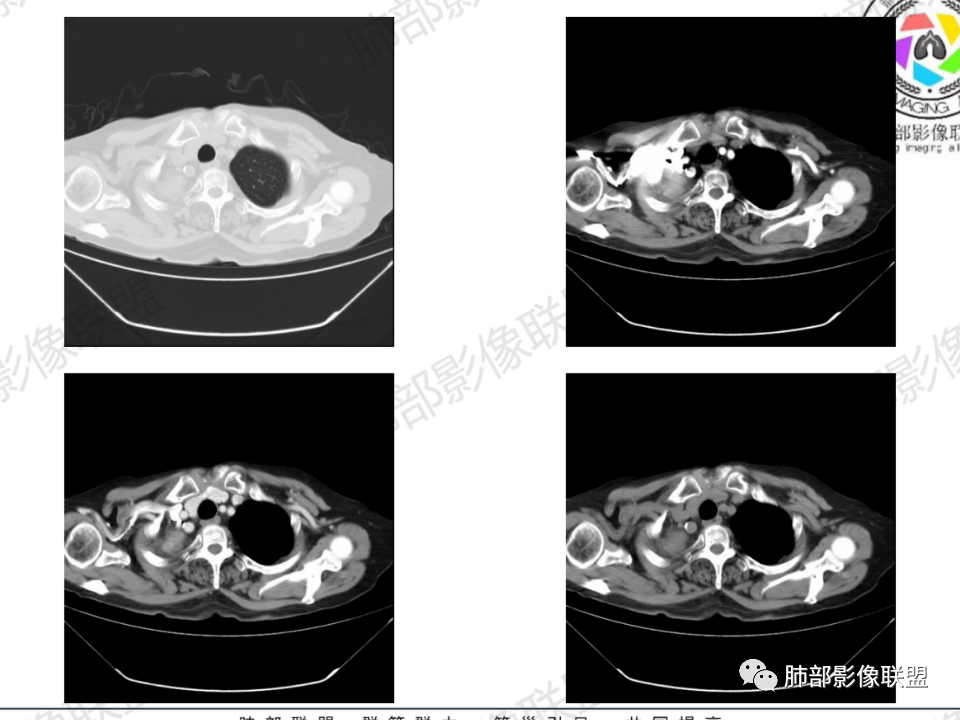

右肺体积小,提示既往结核

支气管影

前,后段都在,没有堵塞

支气管壁增厚,周围磨玻璃边界不清,提示炎症。胸膜下钙化符合结核

近期发热符合感染

这个层面往上应该是尖段,显示不清

背段支气管周围增厚伴钙化,符合结核改变